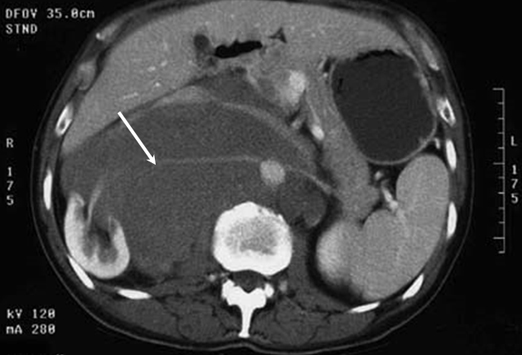

Seminoma:

Seminoma is a germ cell tumour of the testis. About 50 percent of the germ cell tumours detected in the testis are seminoma, but the best thing about them is that they are usually very treatable and curable. A seminoma present in the female ovary is called dysgerminoma, while the one that occurs in the central nervous system is referred to as a germinoma. The most common symptoms of testicular seminoma include testicular and back pain. The average age of the diagnosis of seminoma is 40, and it is usually detected by the presence of placental alkaline phosphatase in the blood.

Image courtesy: diariomedico.com